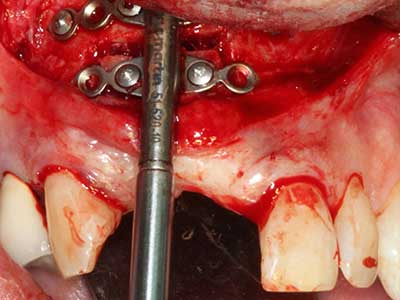

En la extracción de bloques óseos la piezocirugía también presenta ventajas adicionales: Además de la alta precisión en la osteotomía que ya se ha descrito antes, se ha comprobado que el uso de los delgados insertos de sierra resulta especialmente cuidadosas con el hueso. Frente a esto, sobre todo cuando se usan las fresas de Lindemann, cabe esperar pérdidas en la extracción significativamente más altas debido al mayor grosor de la parte frontal del cabezal (Lakshmiganthan, Gokulanathan et al. 2012). La separación basal que se necesita en particular en los injertos de bloque extraídos de forma retromolar se ve facilitada mediante sierras perpendiculares especialmente previstas a tal fin, lo que permite considerar que la cirugía piezoeléctrica es un procedimiento preciso y seguro para la obtención de bloques de hueso en el área retromolar (Happe 2007) (fig. 1-12).

Fig. 1: Preparación de una tapa ósea conforme con Piezomed (W&H, Salzburgo, Austria)

Fig. 3: La separación basal del bloque se ve facilitada con piezas dotadas de una angulación especial.

Fig. 4: Con la rasqueta ósea se obtienen virutas adicionales de hueso autógeno.